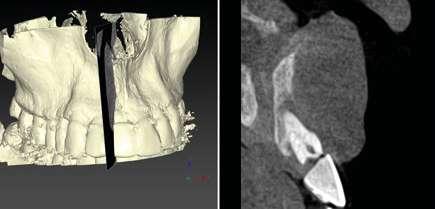

Por otro lado, es imprescindible y fundamental realizar un CBCT de la arcada a tratar para poder visualizar los tejidos duros y hacer una primera valoración del lecho implantario y de la patología existente.

Otra prueba imprescindible hoy en día para nosotros es la realización de un escaneado intraoral que nos aporte la información de los tejidos superficiales y fusionado con el CBCT nos permita valorar los tejidos blandos del paciente.

Para manejar todos estos datos vamos a necesitar de un software de diagnóstico y planificación digital como es el de DTX StudioTM Implant en el cual vamos a abrir tanto el CBCT como el escaneado intraoral y nos va a permitir fusionar ambas mayas utilizando la herramienta SMARTFUSION. En un caso como éste, donde tenemos un incisivo central, superior, derecho, fracturado que vamos a extraer debemos realizar previamente la extracción Virtual en el modelo digital para poder incorporarlo a la planificación de nuestro software.

17.- Verificamos nuestro tratamiento con CBCT.